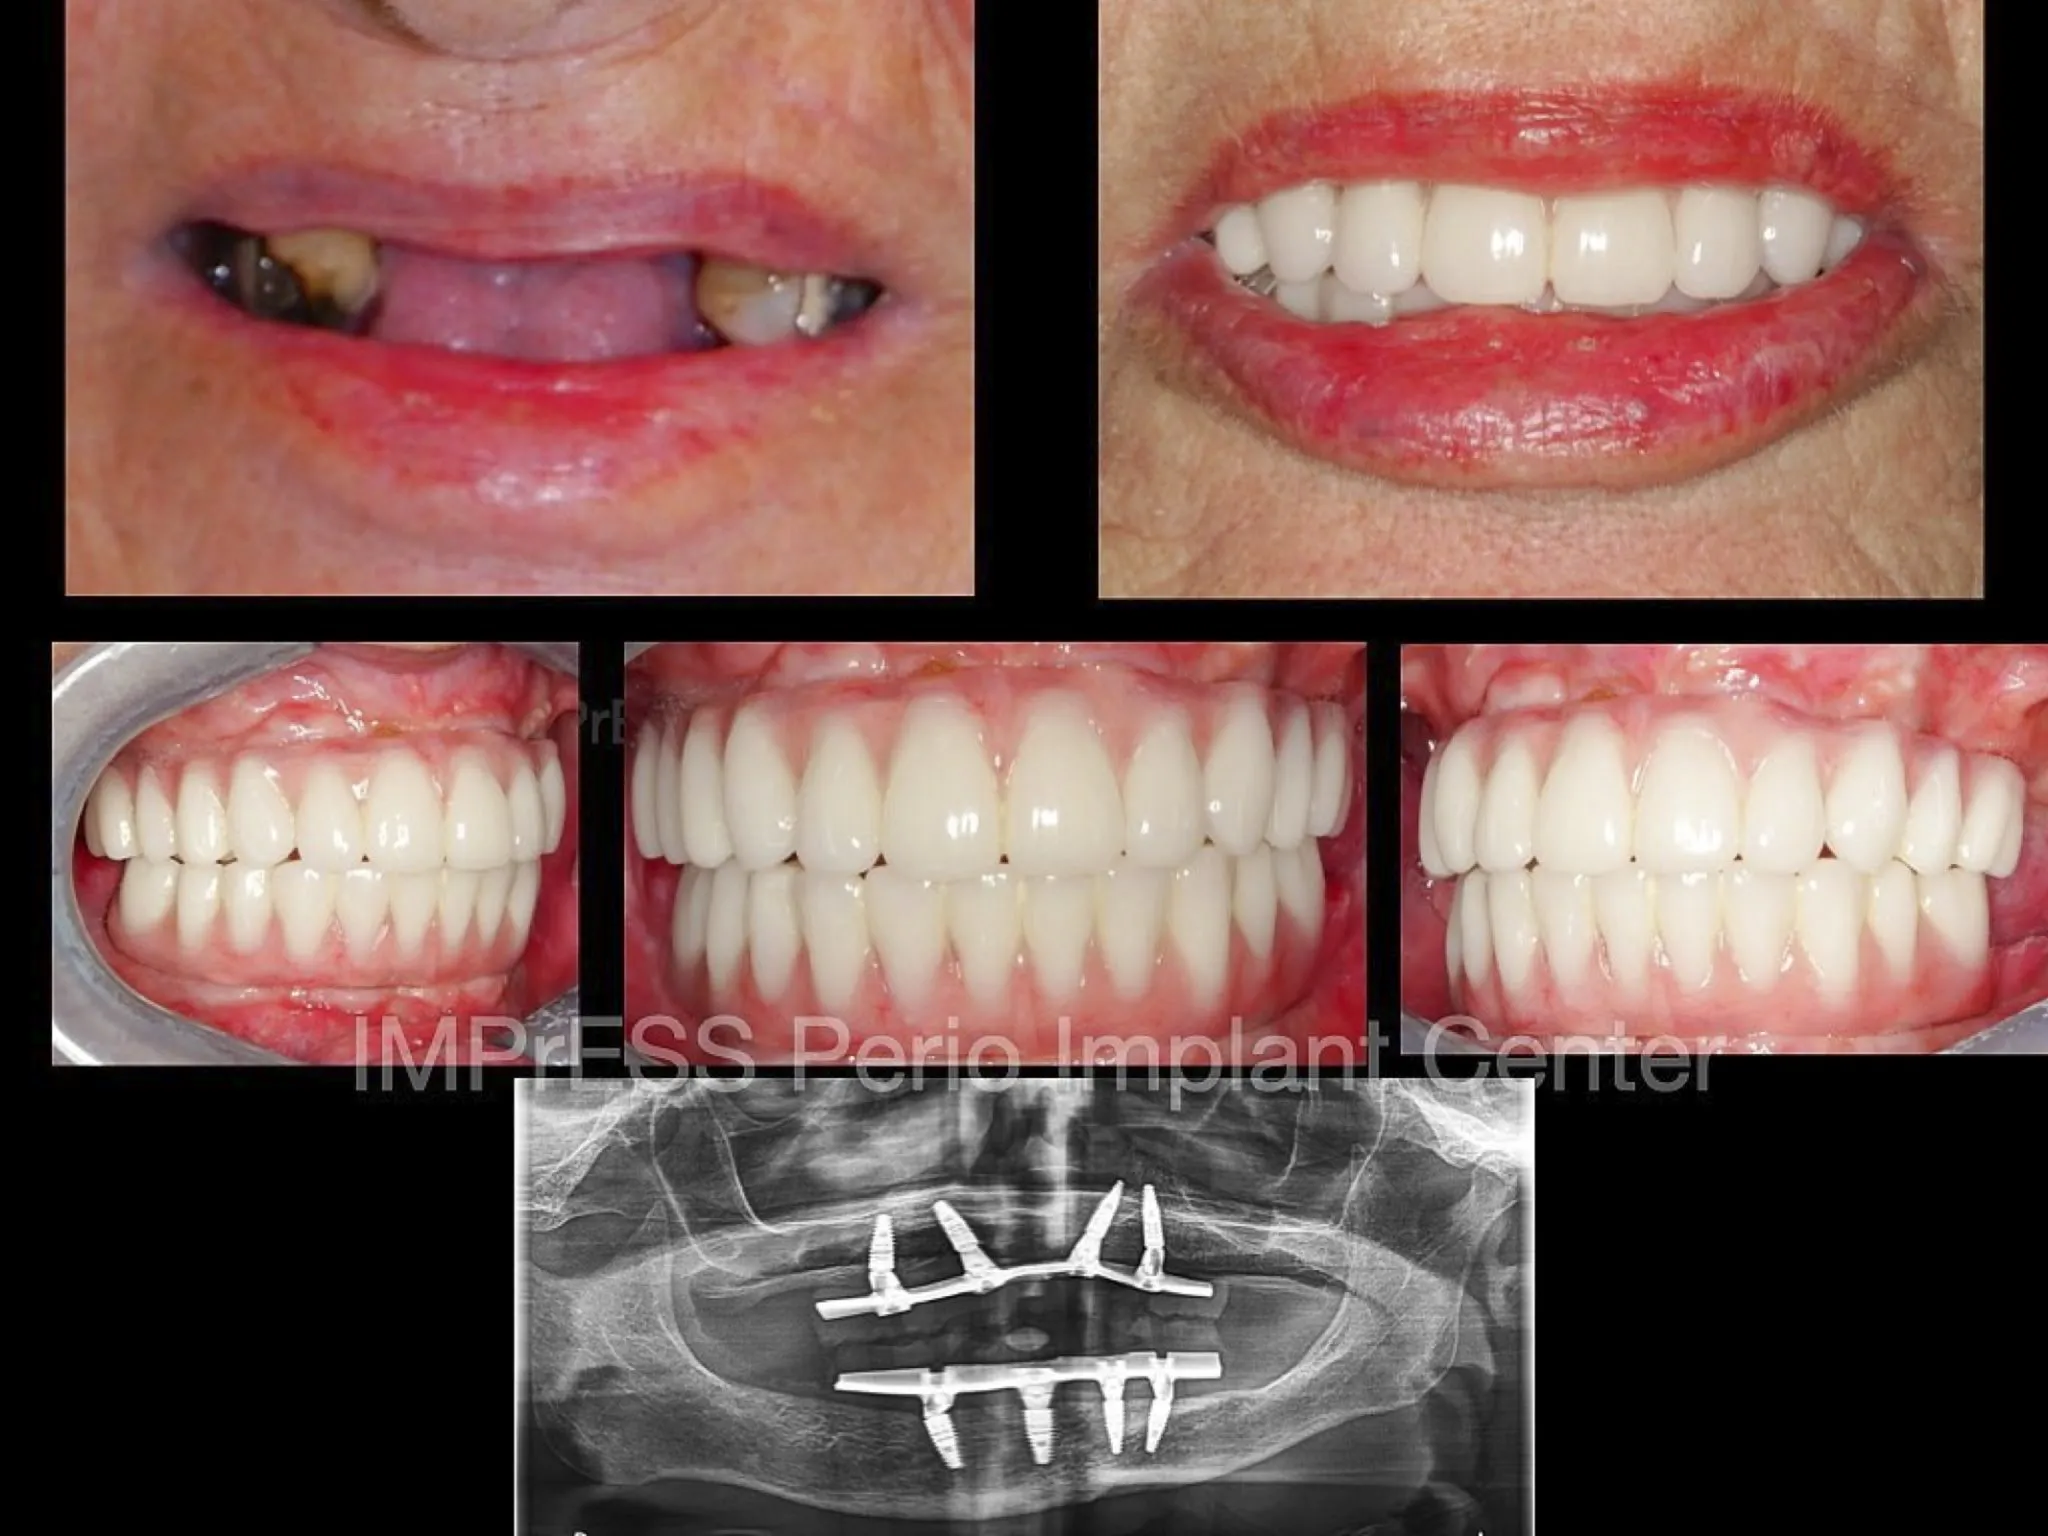

Before & Afters of Dental Implant Patients

Complete Dental Implant Cases Gallery

A minimally invasive solution with a fixed full-arch implant restoration for high patient satisfaction, Fixed (Non-removable) Same-Day-Teeth, providing immediate function and aesthetics

General Disclaimer: The results in the photographs are examples only and do not imply any certainty of the result of a procedure, and all outcomes are subject to the circumstances of the individual patient.